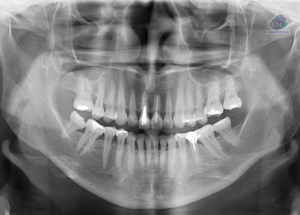

Caso 327 – IDM – OSTEÍTIS CONDENSANTE – IDM

Paciente femenina de 46 años, es referido al Instituto de Diagnóstico Maxilofacial – IDM (Sede Surco) para evaluación general. Radiografia Panorámica En la radiografía panorámica